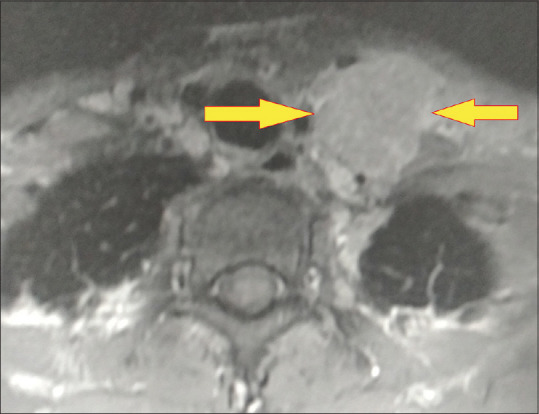

霍奇金淋巴瘤合并结核病是一种极为罕见的临床病例,由于临床表现相似,因此很难处理。本病例报告描述了一名 44 岁男性患者的相同情况,该患者被诊断为科氏淋巴瘤,并在脊柱活检和培养结果证实的基础上开始接受抗结核治疗。尽管接受了结核病治疗,但患者的临床症状仍在恶化。因此,对患者进行了进一步检查,包括纵隔镜检查和支气管内超声检查。从下颈部和纵隔内的聚集性肿块中提取的活检样本显示为结节性硬化型霍奇金淋巴瘤。在接受化疗和放疗以及抗结核治疗后,患者的病情有了明显好转。

Concomitant Hodgkin's lymphoma with tuberculosis is an exceedingly rare clinical scenario and a condition that is difficult to manage due to similar clinical presentation. This case report describes the same in a 44-year-old male patient diagnosed with Koch's and initiated on antituberculosis therapy, based on confirmation of findings from the spine biopsy and culture. The patient's clinical condition worsened despite being on treatment for tuberculosis. Hence, further work up of the patient was done which included mediastinoscopy and endobronchial ultrasound. Biopsy samples from a conglomerate mass in the lower cervical region and mediastinum revealed Hodgkin's lymphoma of the nodular sclerosis type. This time, the patient showed significant improvement following treatment with chemotherapy and radiotherapy along with antituberculosis therapy.